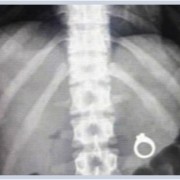

Батерии